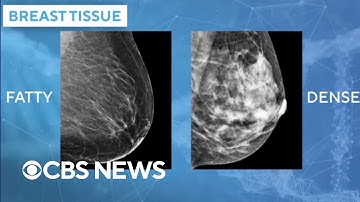

Study says AI better at predicting cancer risk